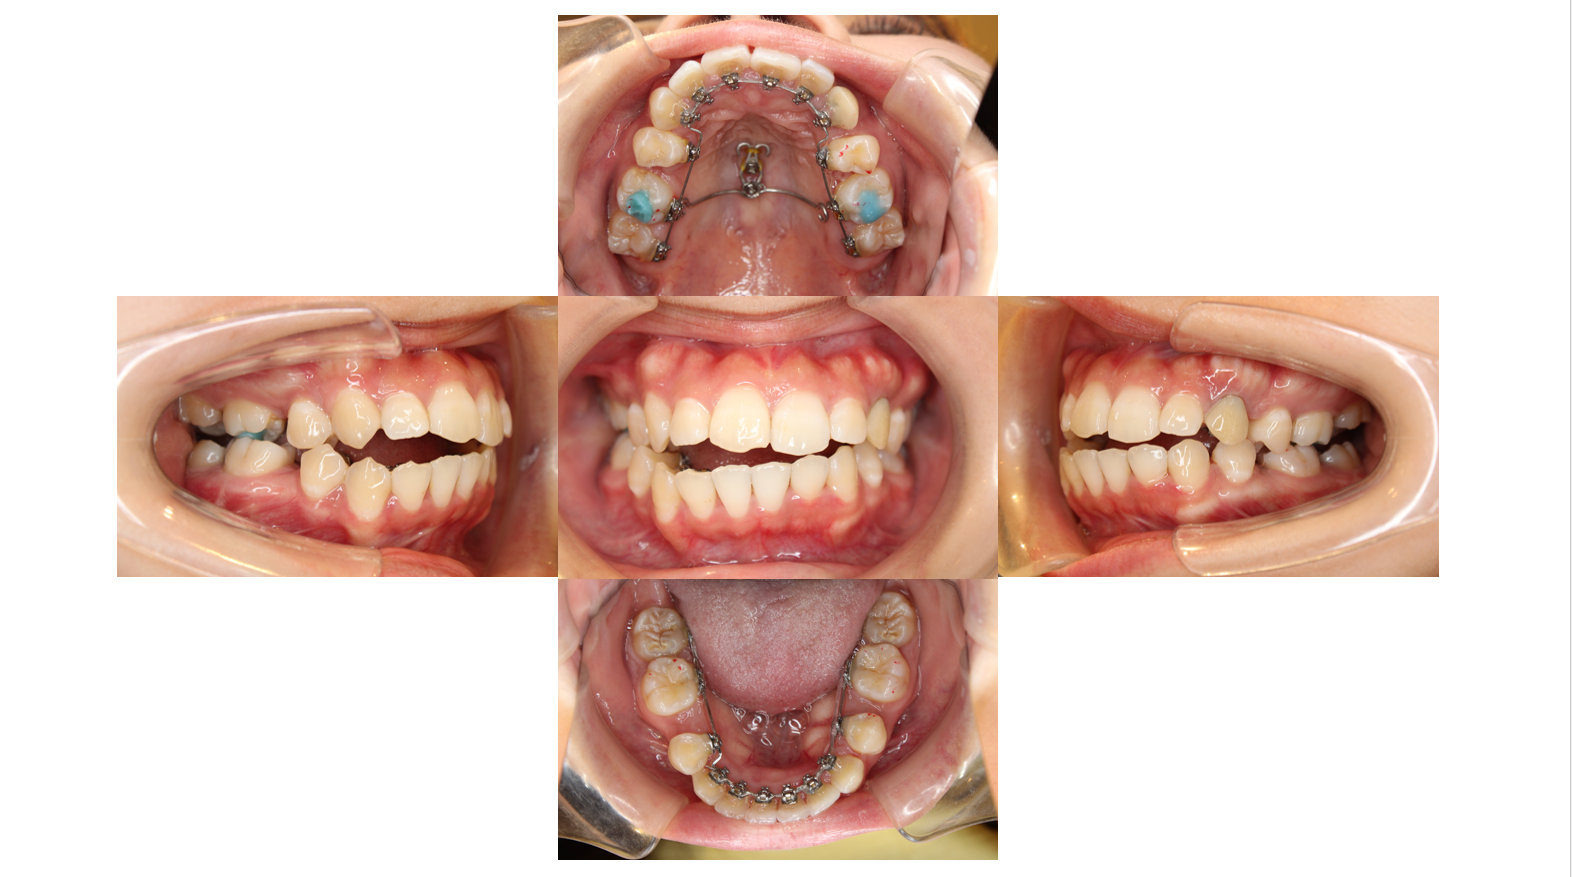

6か月経過

ある程度歯が並んで来たら太いワイヤーに交換していきます

下の歯と装置が当たらないように青い材料を盛ります